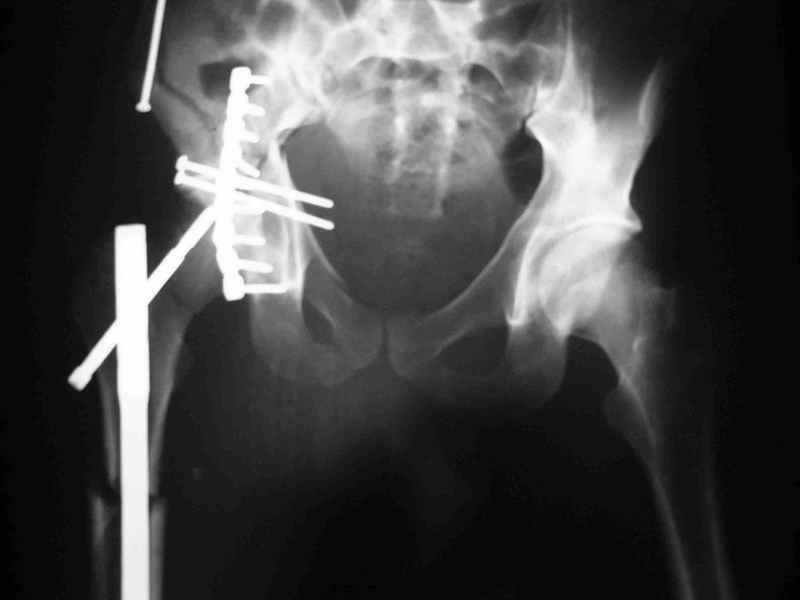

перелом крыла правой подвздошной кости, перелом обеих колонн вертлужной впадины, двусторонний перелом лонных костей (С2.2) повреждение передних связок правого крестцово-подвздошного сочленения,

ипсилатеральный перелом шейки и диафиза бедра.

К сожалению, набора для ретроградного или антеградного реконструктивного штифтования в операционной нет, поэтому доставка заняла н-ное время. Вопрос, который возник у меня- по поводу оптимальной тактики хирургии: вся фиксация в один этап из расширенного доступа или последовательно сначала бедро и позже реконструкция впадины, комбинированный доступ к впадине отдельно к передней и задней колоннам или из расширенного илеофеморального одного доступа. Все-таки решил остановиться на одноэтапном подходе и спустя 5 дней (как раз и наборы привезли) из расширенного илеофеморального доступа сначала фиксировал реконструктивным штифтом Smith&Nephews бедро и

шейку (благо перелом шейки 2 типа -относительно стабильный) затем фрагмент крыла подвздошной кости Lag screw, далее пластина на заднюю колонну и винты в переднюю колонну.(с размерами и направлением винтов ошибка вышла:-((, но интраоперационно у меня была полная уверенность , что винты *ушли* в лонную кость).